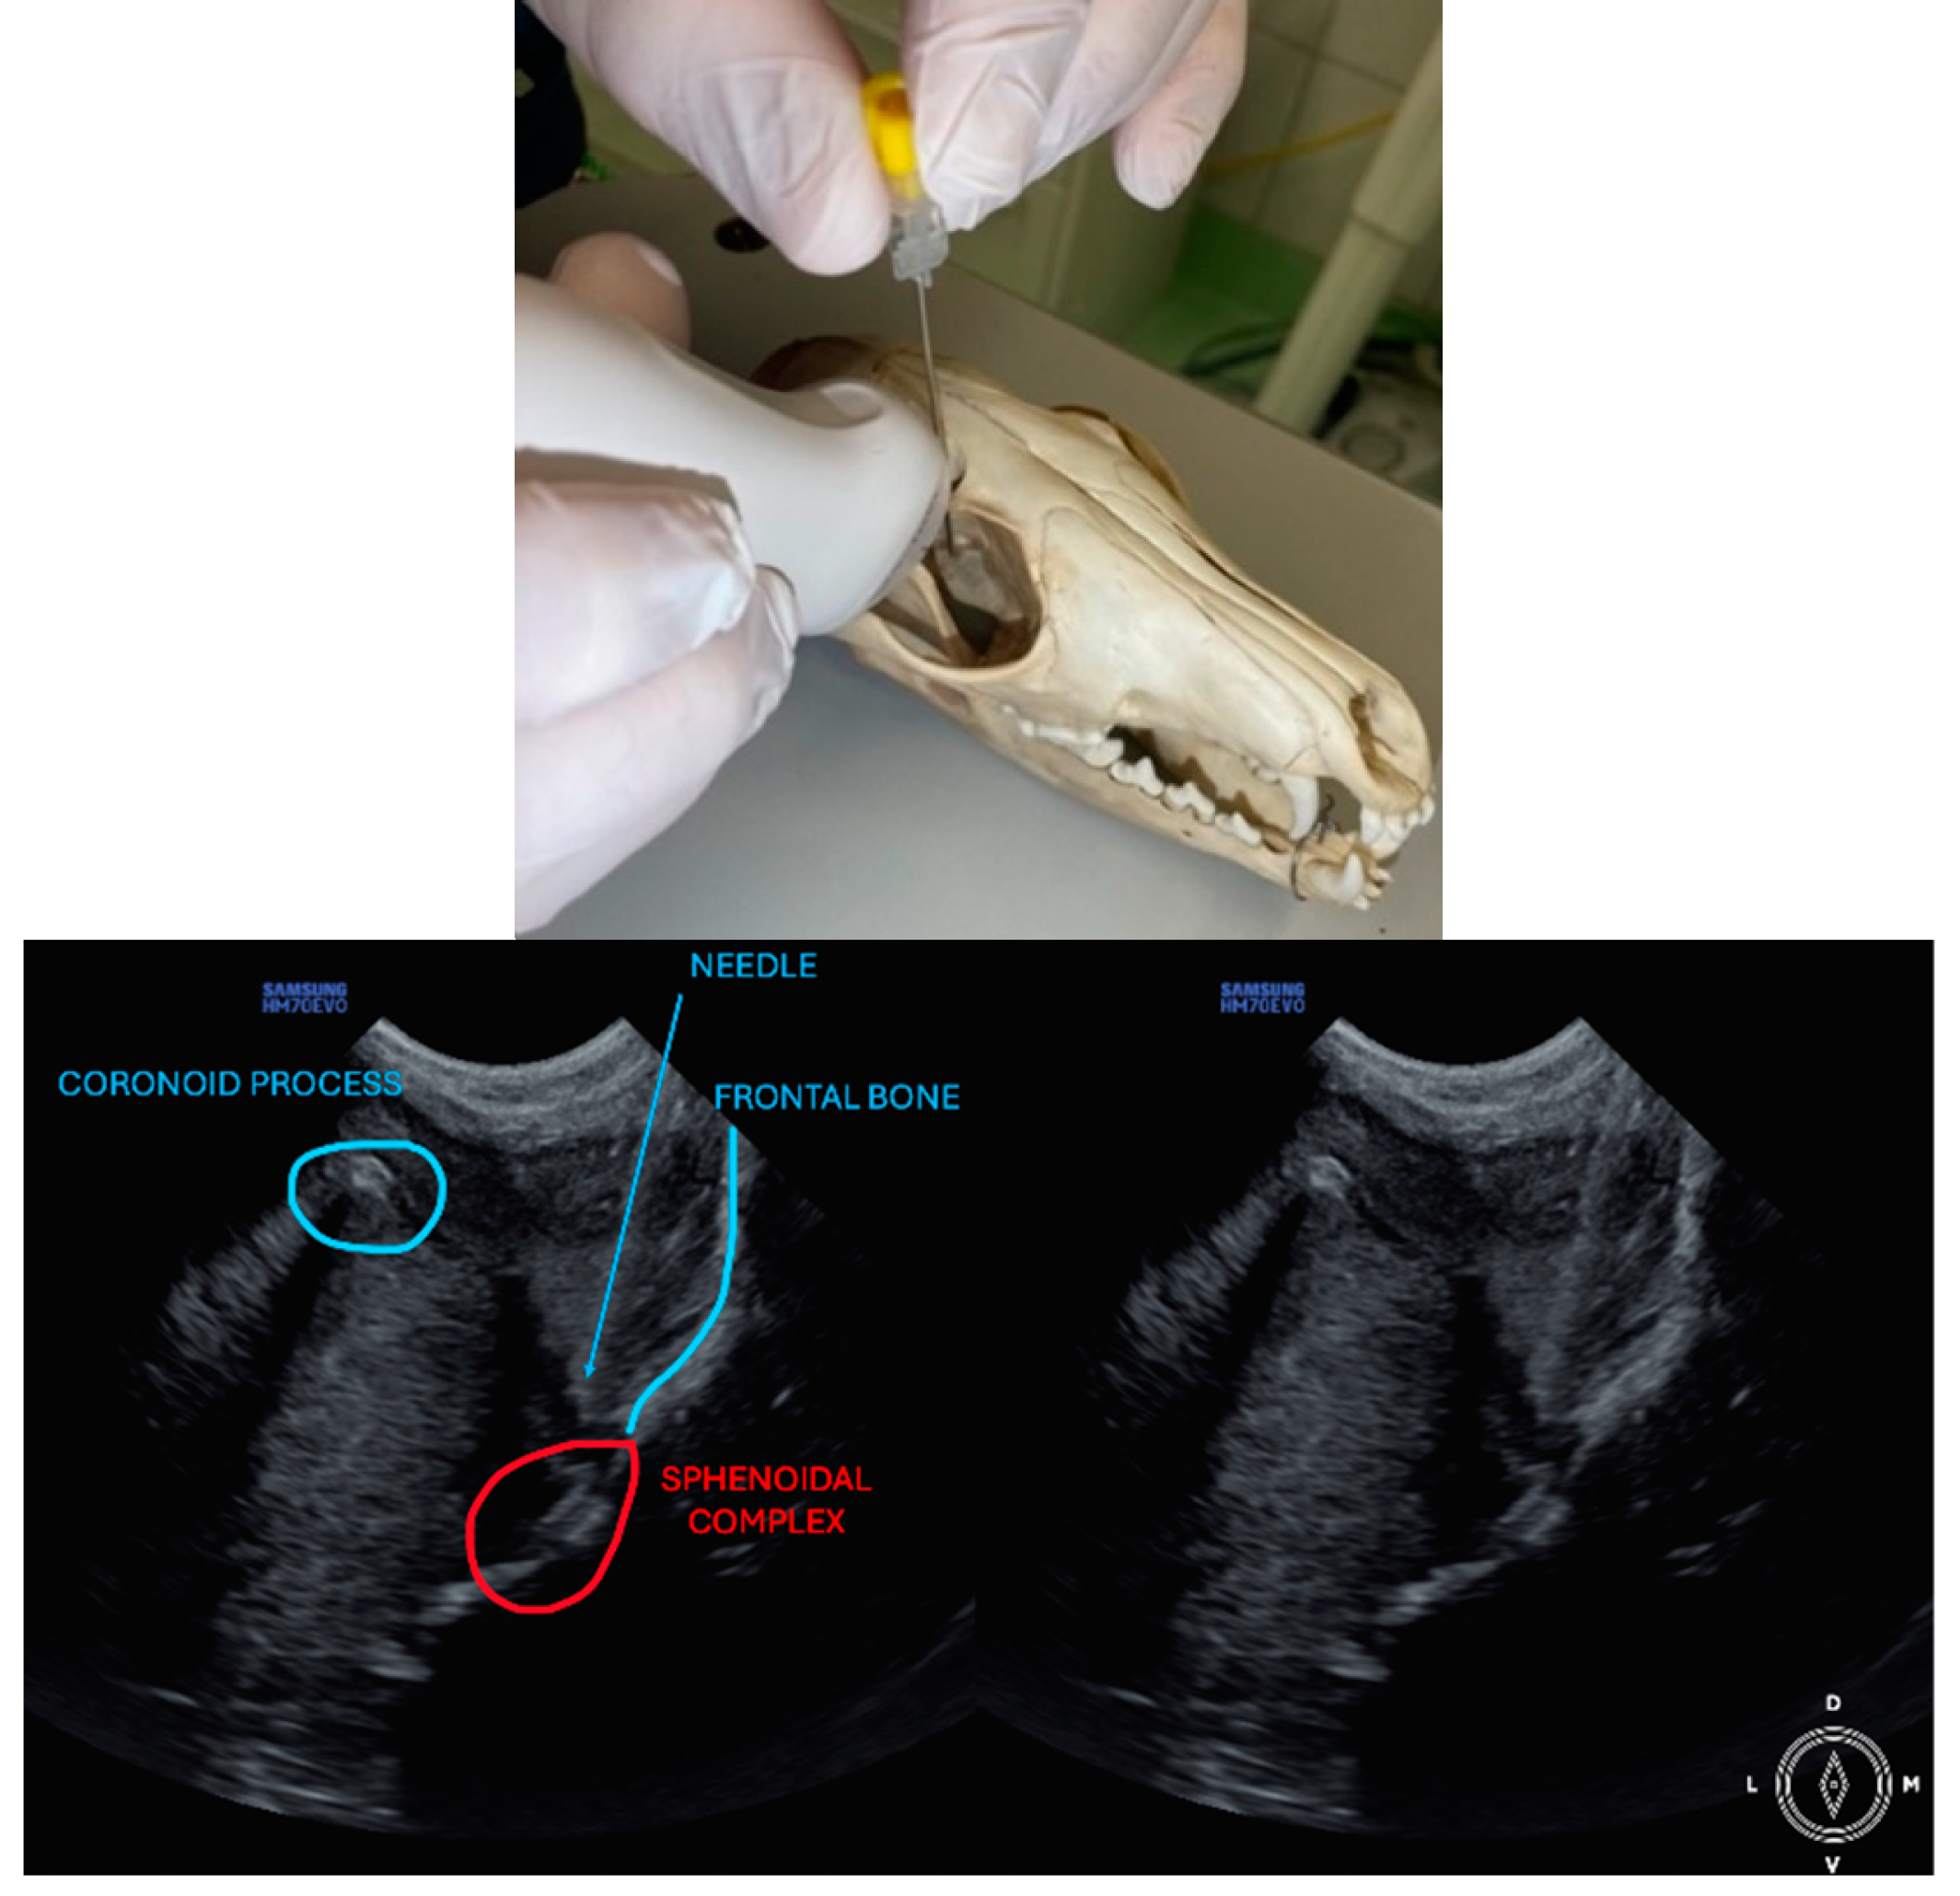

The ultrasound probe was positioned over the temporal region immediately caudal to the orbital ligament to obtain a transverse view of the caudal portion of the pterygopalatine fossa for both approaches. Slight tilting movements adjusted the probe until the following structures were identified: the frontal bone was observed as a hyperechogenic continuous line, which in the deep aspect of the pterygopalatine fossa showed an irregular structure consistent with the sphenoidal complex (optic canal, orbital fissure, and rostral alar canal). The coronoid process was also identified as a sharp, small, strongly reflective, hyperechogenic structure casting a strong acoustic shadow through the fossa (Figure 1 and Figure 2).

Description of coronoid approach: the dog’s mouth was opened with a mouth gag to expose the mandibular notch and facilitate the insertion of the needle, from lateral to medial, just ventral to the zygomatic arch and cranial to the temporomandibular joint (Figure 2). The needle was inserted using an in-plane approach, from lateral to medial direction until its tip was positioned near the sphenoidal complex, where the calculated volume was injected.

Figure 2. Position of the probe and the needle. Ultrasound image of the coronoid approach.